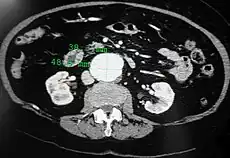

A transverse contrast enhanced CT scan demonstrating an abdominal aortic aneurysm of 4.8 by 3.8 cm

The standard aortic measurement on abdominal ultrasonography, such as used for abdominal aortic aneurysms, is between the outer margins of the aortic wall.[3]